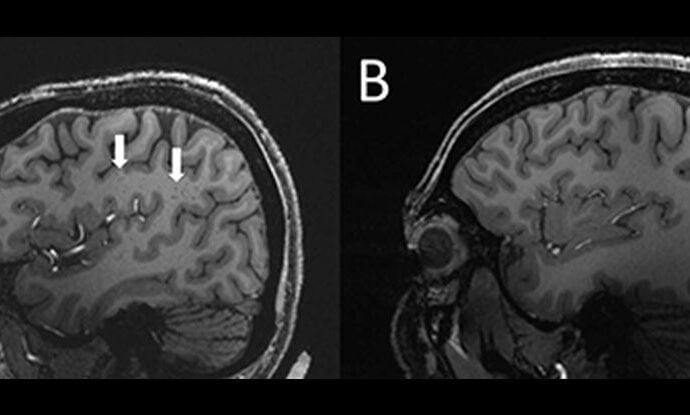

Os cientistas podem ter acabado de encontrar uma nova pista importante que pode ajudar a resolver o mistério frustrante e contínuo da enxaqueca. Com informações de Science Alert. Usando ressonância magnética de ultra-alta resolução , os pesquisadores descobriram que os espaços perivasculares – espaços cheios de líquido ao redor dos vasos sanguíneosContinue Reading